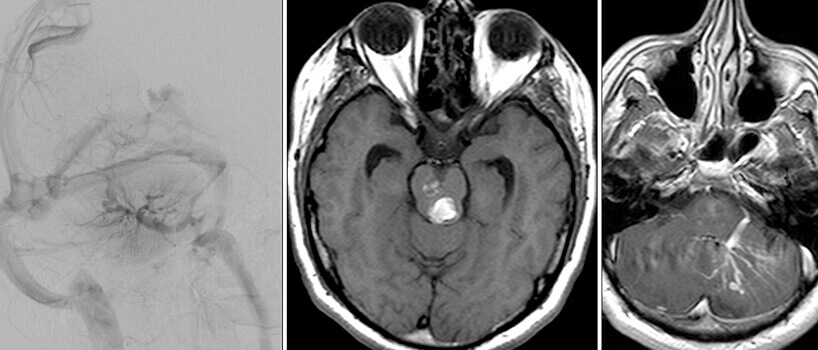

Είναι καλοήθεις δυσπλασίες στο φλεβικό σκέλος, με σηραγγώδεις φλεβικές λιμνάσεις, χωρίς αρτηριοφλεβώδη επικοινωνία. Μπορεί να είναι μονήρεις (σποραδική μορφή) ή πολλαπλές. Στην τελευταία περίπτωση είναι συνήθως οικογενείς και κληρονομούνται κατά τον αυτοσωματικό επικρατούντα χαρακτήρα (χρωμόσωματα 7q21-22(CCM1), 7p13-15(CCM2) και 3q25-27(CCM3)).

Αυξάνονται σε μέγεθος μετά από επεισόδια αιμορραγίας λόγω υποτροπιαζόντων, συρρρεόντων μικροαιματωμάτων που συμβαίνουν σε διαφορετικές χρονικές περιόδους. Εντός της βλάβης διακρίνονται αιμορραγικά στοιχεία σε διαφορετικά χρονικά στάδια (παλαιότερα και πιό πρόσφατα).